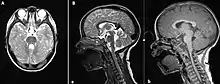

(A) MRI of the brain (sagittal section) showing vermal hypoplasia predominantly on the upper levels; (B) Cerebral MRI (axial section) in T1 and T2 showing the enlargement of the upper cerebellar peduncles with the characteristic "molar tooth" appearance.

The disorder is characterized by absence or underdevelopment of the cerebellar vermis and a malformed brain stem (molar tooth sign), both of which can be visualized on a transverse view of head MRI scan.[16] Together with this sign, the diagnosis is based on the physical symptoms and genetic testing for mutations. If the gene mutations have been identified in a family member, prenatal or carrier diagnosis can be pursued.[4]